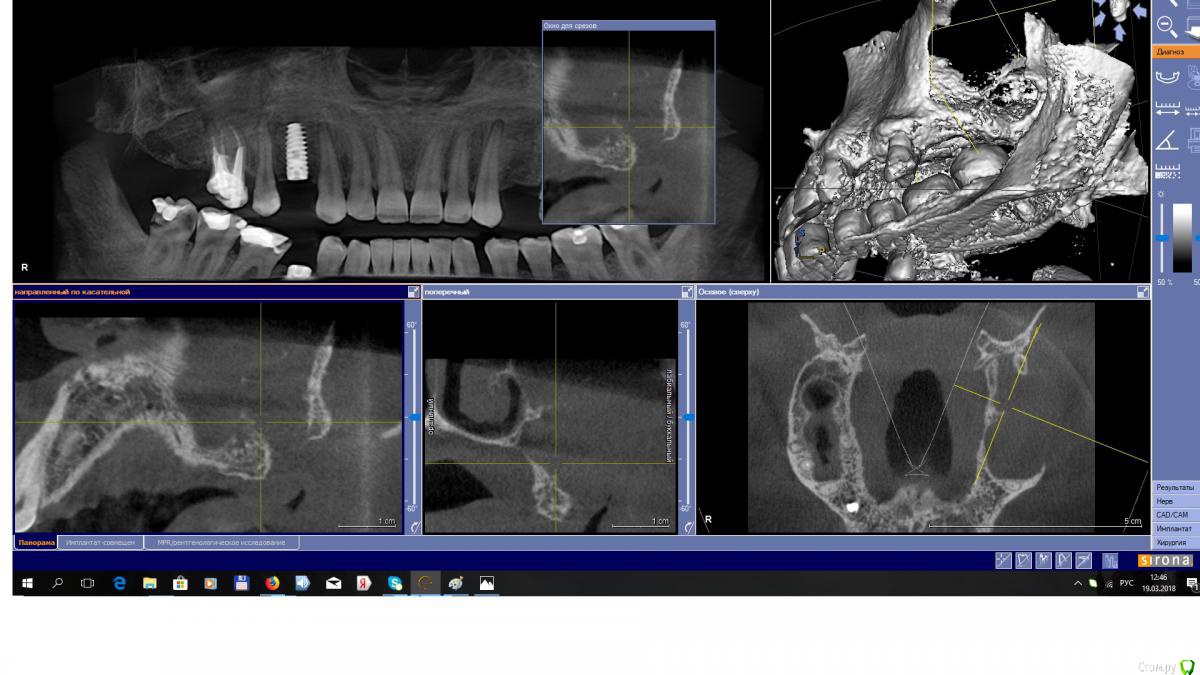

EEcho Опубликовано 19 марта, 2018 Поделиться Опубликовано 19 марта, 2018 Добрый вечер , коллеги.Ваше мнение ?Пациент обратился в 2014г. , поставить импланты во втором сегменте.На КТ обнаружилась такая картина. Был отправлен к ЛОРу. , пациент к нему сразу не пошел, потом и вовсе пропал.А тут появился с желанием опять поставить импланты. новый снимок он пока не делал, и к ЛОРу он то же так и не ходил.Вопрос, что в том случае делать? Ссылка на комментарий

EEcho Опубликовано 20 марта, 2018 Автор Поделиться Опубликовано 20 марта, 2018 Да на реверс , это понятно, Но , если гипотетически, он пойдет к ЛОРу , пролечит пазуху, А дальше?Я делал синус с резными ситуациями, с разными дефектами, опыт есть, но с таким отсутствием стенки пазухи сталкиваюсь впервые.Поэтому в затруднении, как в при таком дефекте закрыть окно, применять ли сетку, или мини пластины, или ламину?Интересно, кто сталкивался с таким, что делал и отдаленные результаты. Ссылка на комментарий

Irouil Опубликовано 20 марта, 2018 Поделиться Опубликовано 20 марта, 2018 (изменено) Найти того, кто готов это разобщить все. Псков недалеко от Петербурга, есть тут один доктор, даже видосики выкладывал со схожими дырками. Ну, или разобщать самостоятельно. Но это все только с условием, что в пазухе действительно рецидив после колдвел/люка, а не онко. Проверьте, кстати, есть там дырка в нижнем носовом ходе? Теоретически ещё могли так 2.8 удалить Изменено 20 марта, 2018 пользователем Irouil Ссылка на комментарий

EEcho Опубликовано 20 марта, 2018 Автор Поделиться Опубликовано 20 марта, 2018 Да Найти того, кто готов это разобщить все. Псков недалеко от Петербурга, есть тут один доктор, даже видосики выкладывал со схожими дырками.Ну, или разобщать самостоятельно. Но это все только с условием, что в пазухе действительно рецидив после колдвел/люка, а не онко.Проверьте, кстати, есть там дырка в нижнем носовом ходе?Теоретически ещё могли так 2.8 удалитьДа, сейчас будем обследовать пациента полностью.подозрение на онко возникло сразу еще 2014 году, но он ни куда не обращался, с тех пор его ни чего не беспокоит, и во рту то же все хорошо.со слов, ему так удалили 28, возможно бугром, после этого он лежал в ЧЛХа , что там делали не помнит.Доктора можно поискать в архиве? Ссылка на комментарий

Bier Опубликовано 23 марта, 2018 Поделиться Опубликовано 23 марта, 2018 посмотрел, мощная дыра. Надо понять, что там в пазухе, если рубцы, но на мой взгляд необходимо на первой операции вычистить пазуху и изолировать ее от полости рта, например, титановой фольгой. На второй операции, после восстановления слизистой проводить синуслифтинг. Ссылка на комментарий